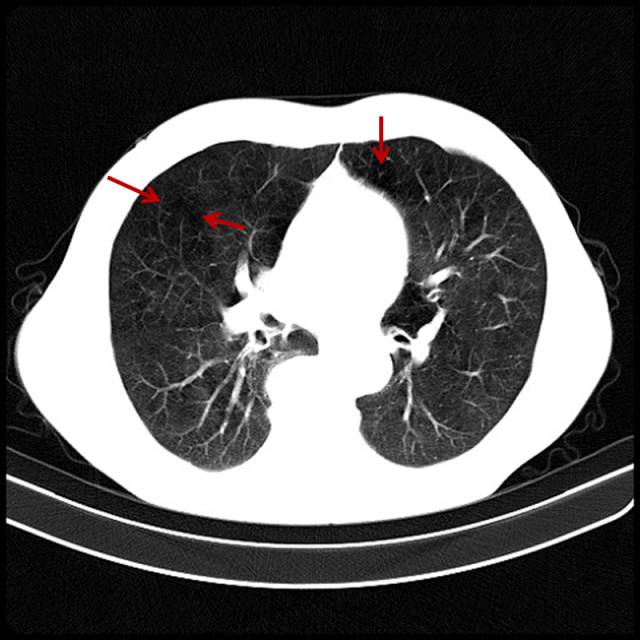

吸烟导致的轻度肺气肿

男,32岁,16岁开始吸烟。

图片

图5

肺的周边密度已经变低,周边纹理变细、消失,这时肺功能受到影响,详细询问病史,有气短症状。比如原来上五层楼气喘吁吁,现在上三层楼既能感到上气不接下气,症状往往被忽略,尤其是年轻人,不会以为自己吸烟会得肺气肿,这部分人也是最难戒掉烟的。与这类患者交谈时,也知道吸烟不好,但往往不以为然。此类患者多见于年轻人,属于亚临床患者。